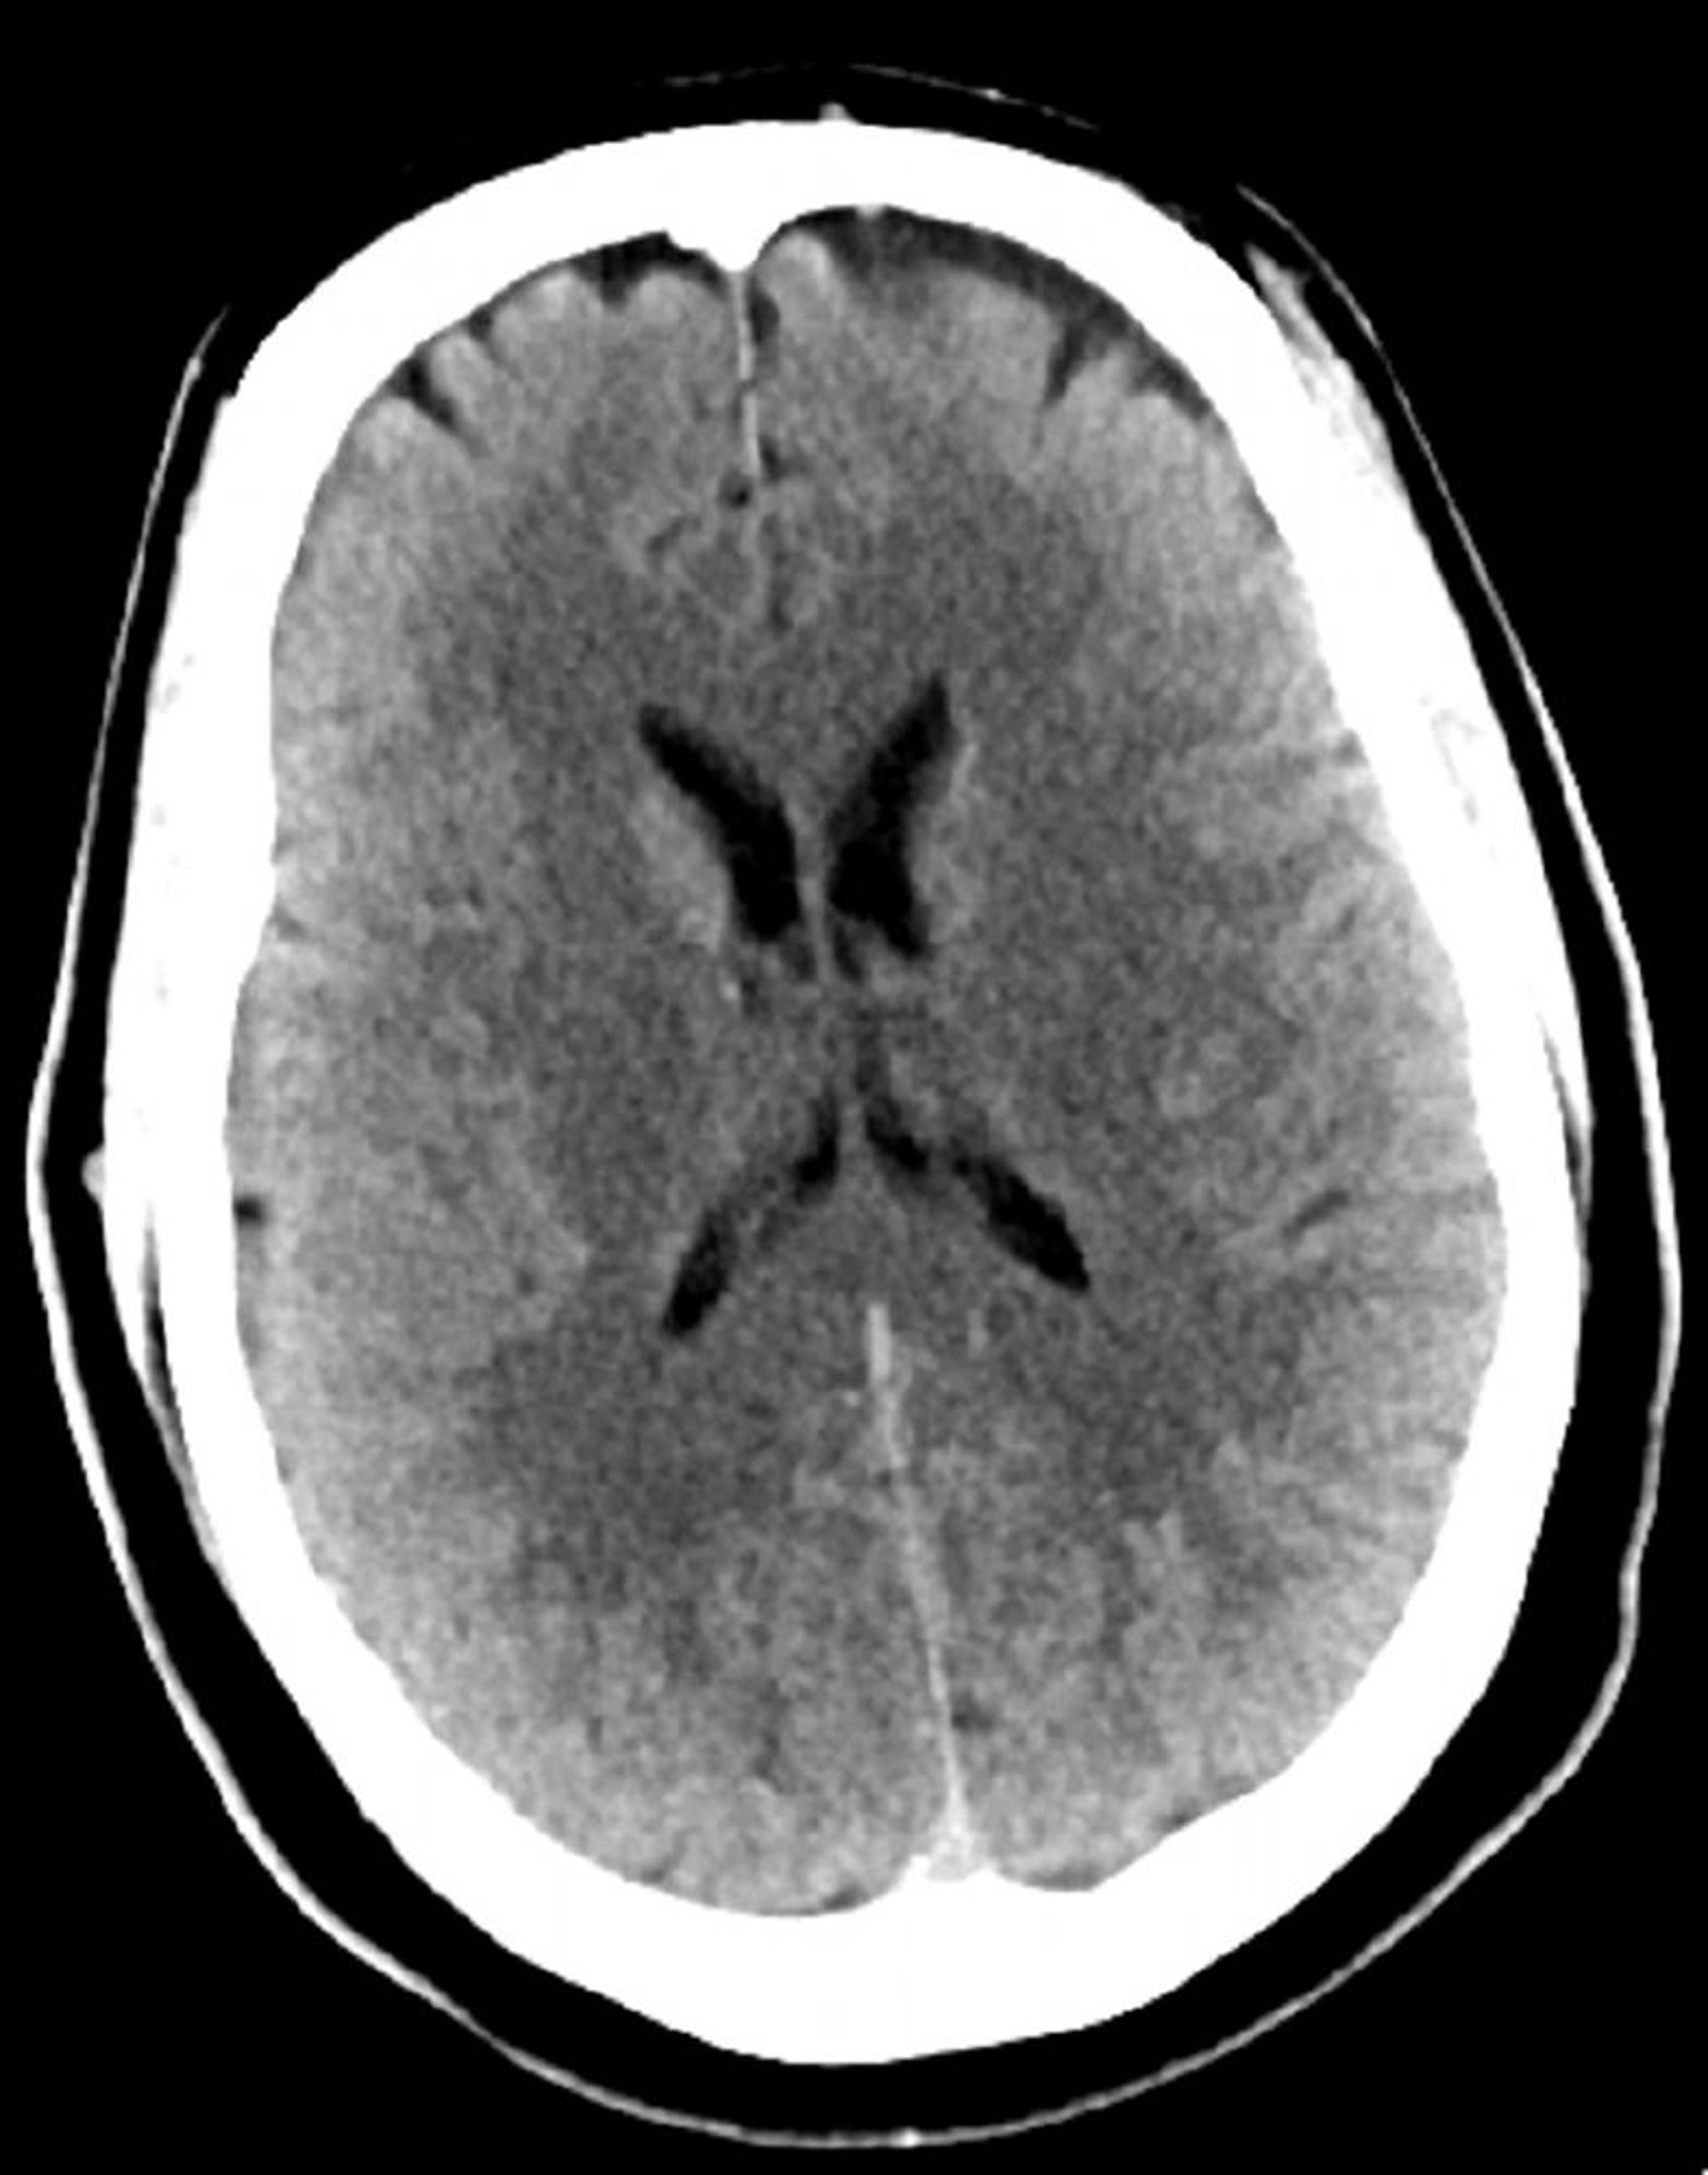

TC de crânio normal (adulto, idade 30) – – Diapositivo 4

Essa é uma TC normal da cabeça de um adulto jovem com 30 anos. Não há líquido ou hemorragia intra ou extra axial. A diferenciação cinza-branco é preservada. O tamanho ventricular e o padrão dos sulcos parecem normais.